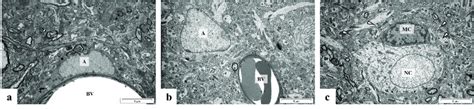

Immunohistochemical Analysis Of The Rat Hippocampal Ca1 Region A The

• Microphotographs (40×) Of Hippocampal Ca1 Region (a, B) And The Fifth ...